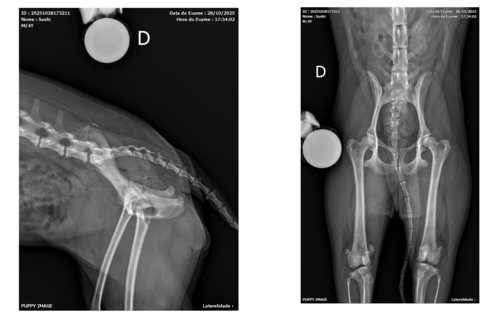

Também sou quadrinista e tenho 3 lulus da pomerânia. Uma deles, que é a minha cachorrinha Sushi, vai precisar operar a patela (joelho) porque ela está com luxação de patela no grau 3-4. São 4 graus de gravidade, então a melhor decisão no momento seria operar a patinha dela, não tem jeito.

Quando o bichinho tem luxação de patela em graus mais baixos, a patela desloca, mas logo volta ao lugar. O que não é mais o caso da Sushi :( Olha como está a patinha dela:

No dia, corri para a clínica veterinária, ainda com a pata dela nesse estado e fizemos o raio x para ver se não tinha rompido nenhum ligamento. Não rompeu, mas a luxação na patela estava MUITO grave e a outra patinha também está já com a luxação. Vamos avaliar amanhã na sexta (dia 31 de outubro) se será necessário operar as duas patas.